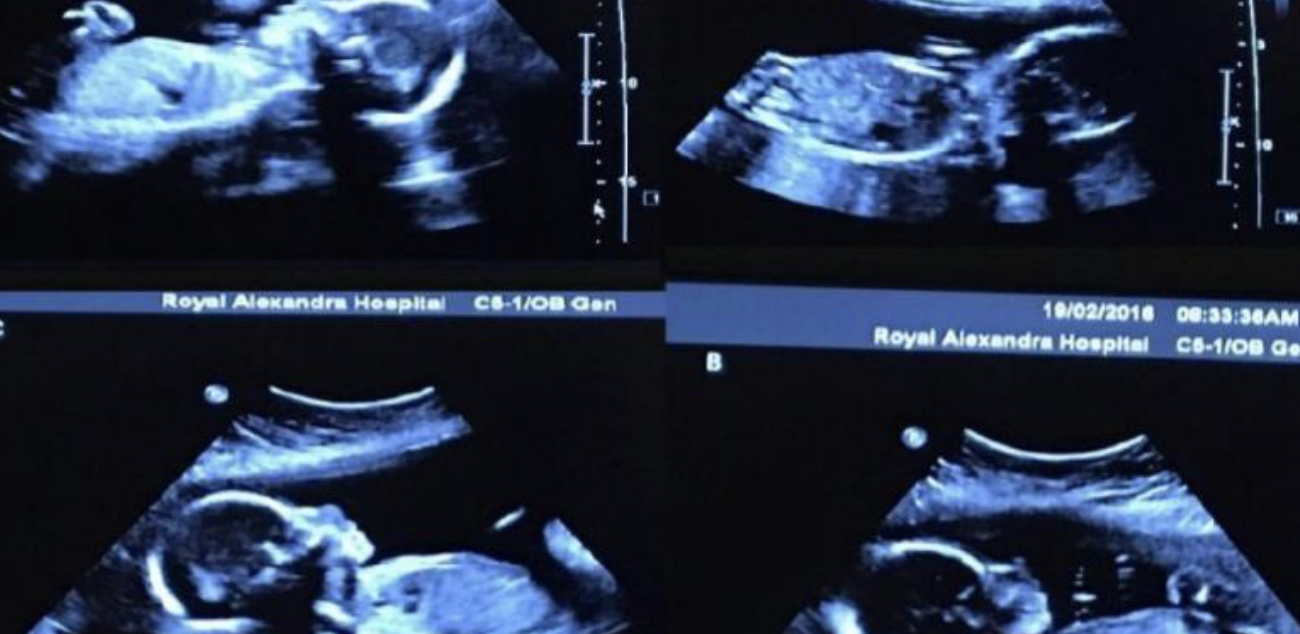

After the examination, the couple learned that Bettany was pregnant. It was something the couple didn’t expect even in their wildest dreams. It’s only been three months since their wedding, and they’re about to welcome another family member. What happiness! Well, the most startling fact was yet to be revealed. Contrary to all doubts and assumptions, the birth went smoothly.

Doctors did not allow Bettany to give birth on her own, as it could be dangerous for her children. Therefore, they opted for a caesarean section at 33 weeks. Children came into the world on May 6, 2016. Another surprise was that all the children were girls. Children became famous before they were born, and now that they were born, people from all over their hometown came to admire them.